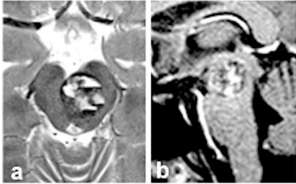

未料观察期间的爱丽丝再次遭遇打击。一年后,爱丽丝再次出现头痛、复视和轻微运动无力。担忧之事终究发生。与之前不同的是,此次她整个右侧身体开始无力。入院检查发现脑干再次出血,MRI显示脑干中脑海绵状血管瘤尺寸达20mm(图a和b)。

图a和b:术前轴向(a)和矢状(b)MRI